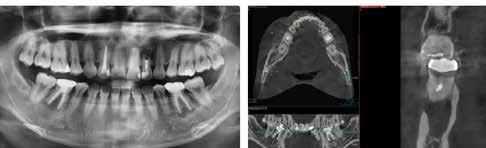

1. a–d. ábra: Műtét előtti állapot mind a négy páciensnél. 1. eset (a). 2. eset (b). 3. eset (c). 4. eset (d).

Az alábbi esettanulmányhoz négy pácienst választottunk ki (1. táblázat). Minden esetben egy, vagy több fog pótlására volt szükség, amelyhez kerámiaimplantátumokat használtunk. Valamennyi páciens általános egészségügyi állapota jó volt.

A pótlásra szoruló fogat, vagy fogakat minden esetben legalább egy évvel a fogpótlást megelőzően eltávolítottuk. Ezen esetek egyikében sem végeztünk alveolus vagy állcsontgerinc prezervációt az eltávolítás során, illetve minden páciens jó szájhigiéniával rendelkezett. Egy kivételével minden páciensnél radiológiai analízist végeztünk CBCT-vel, amelyet

digitális implantátumtervezés követett (SICAT és Sidexis, mindkettő Dentsply Sirona; 1. ábra).

3. a–b ábra: Röntgenfelvételek három hónap után (a) és a gyógyulási csavarok behelyezve (b, 1. eset).

4. a–b ábra: Röntgenfelvételek öt hónappal később (a) és a gyógyulási csavarok behelyezve (b, 2. eset).

5. a–c ábra: Röntgenfelvételek öt hónappal később (a) és a gyógyulási csavarok behelyezve (b és c, 3. eset).

6. a–b ábra: Röntgenfelvételek öt hónappal később (a) és a gyógyulási csavarok behelyezve (b, 4. eset).